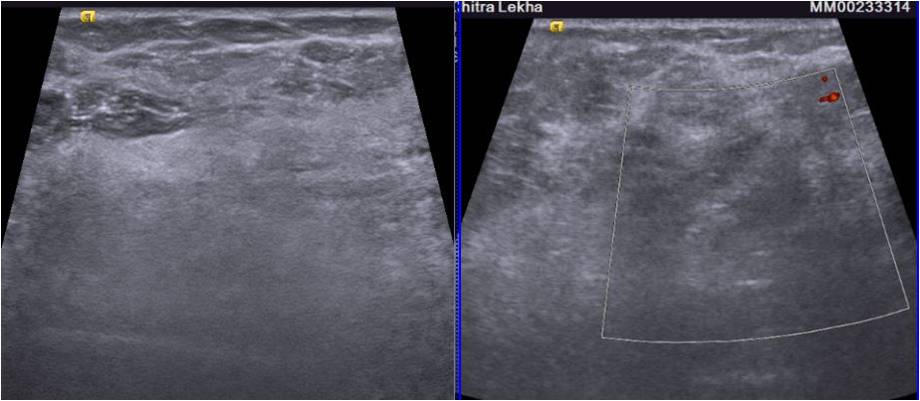

Screening mammogram MLO view revealed an area of focal asymmetry in the right breast in the form of multiple linear densities involving the upper outer quadrant. Spot compression CC view in the area of focal asymmetry shows that the asymmetric density does not disappear on compression. •A prominent axillary lymph node is seen with maintained fatty hilum and normal cortical thickness. A High-resolution Ultrasound of the breast showed an ill-defined area of hyperechogenicity in the right upper outer quadrant.  No significant internal vascularity was seen on color doppler images. On contrast enhanced MR images a large area of heterogeneous, non mass like enhancement is seen in regional distribution involving upper outer quadrant of right breast. Linear extension of enhancement is seen in breast parenchyma with intervening normal breast tissue. Infiltration of underlying pectoral muscles is also noted. Ultrasound guided biopsy is done on the account of the presence of suspicious Imaging findings.  The area of focal asymmetry on mammography revealed multiple linear shadows On ultrasound, an area of focal abnormal hyperechogenicity with indistinct margins was seen. The lesion was ill-defined with non circumscribed margins which raised the suspicion of a sinister pathology. Contrast enhanced MRI breast was performed to assess nature and extent of disease. It confirmed the infiltrative nature of the disease and involvement of the pectoralis muscle •On histopathology, a diagnosis of invasive lobular carcinoma was made. The node’s FNAC revealed a reactive node